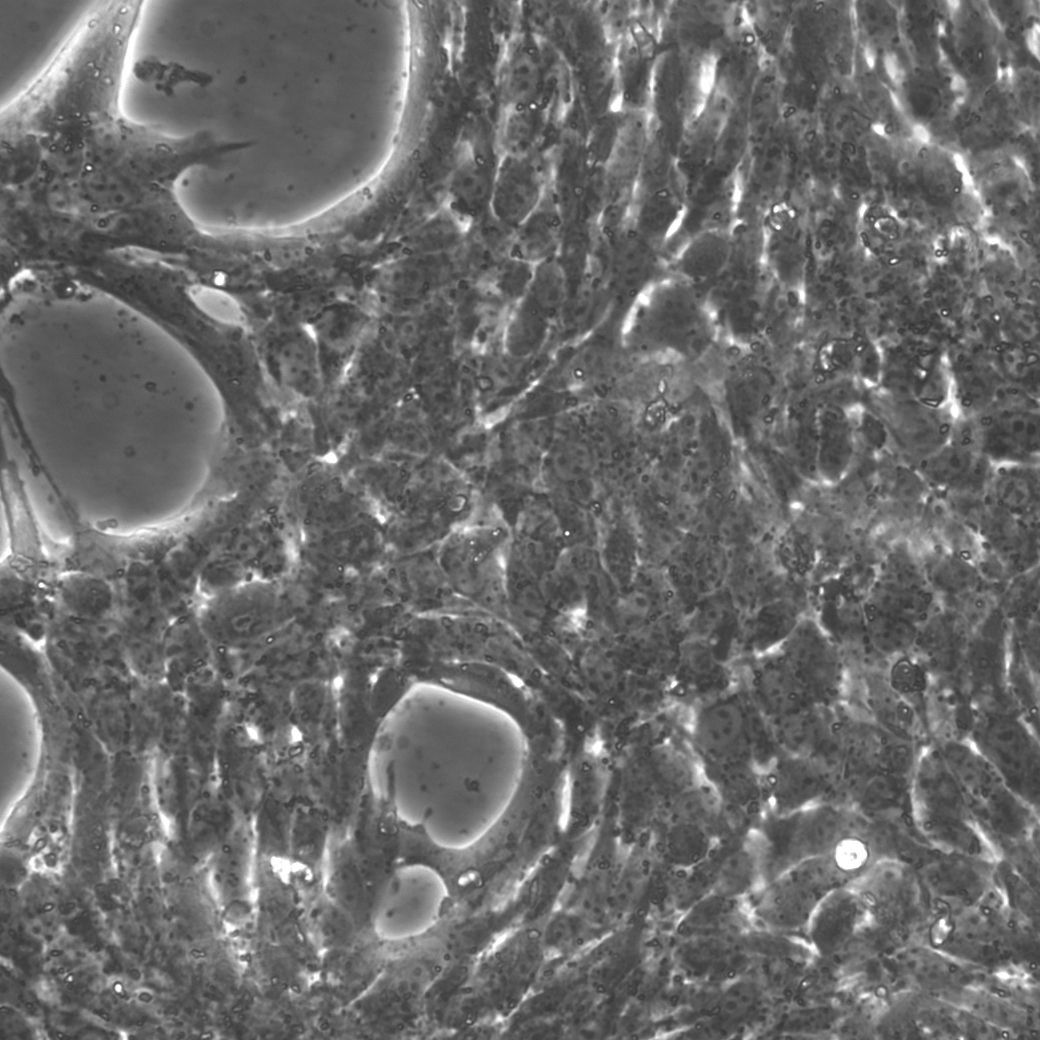

上皮样细胞,贴壁生长 |

来源于 C57BL/6J小鼠的原发性肝细胞癌,这些小鼠肝细胞忠实地代表了肝细胞癌,并为研究这种类型的肝癌提供了有价值的模型,同义词HEP-53.4和53.4,它们便于识别和交叉引用,肝细胞癌是一个重大的健康问题,这些细胞能够对其分子通路、细胞相互作用和治疗策略进行精确研究,这些细胞起源于Mus musculus(小鼠),为理解和开发肝细胞癌的治疗方法提供了相关的模型系统。 |